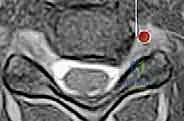

- التصوير بالرنين المغناطيسي (MRI): وهو الفحص الأهم لتحديد موقع الانزلاق الغضروفي بدقة ومدى انضغاط الأعصاب.

- التصوير المقطعي (CT Scan): قد يُطلب للحصول على تفاصيل أدق للتشريح العظمي.

يحدث عندما تتمزق الحلقة الليفية الخارجية للقرص، مما يسمح للمادة الهلامية الداخلية (النواة اللبية) بالبروز والضغط المباشر على العصب الشوكي المجاور أو الحبل الشوكي نفسه.

تختلف الأعراض بناءً على ما إذا كان الضغط واقعاً على جذر عصب واحد (اعتلال الجذور العصبية - Radiculopathy) أو على الحبل الشوكي بأكمله (اعتلال النخاع - Myelopathy).